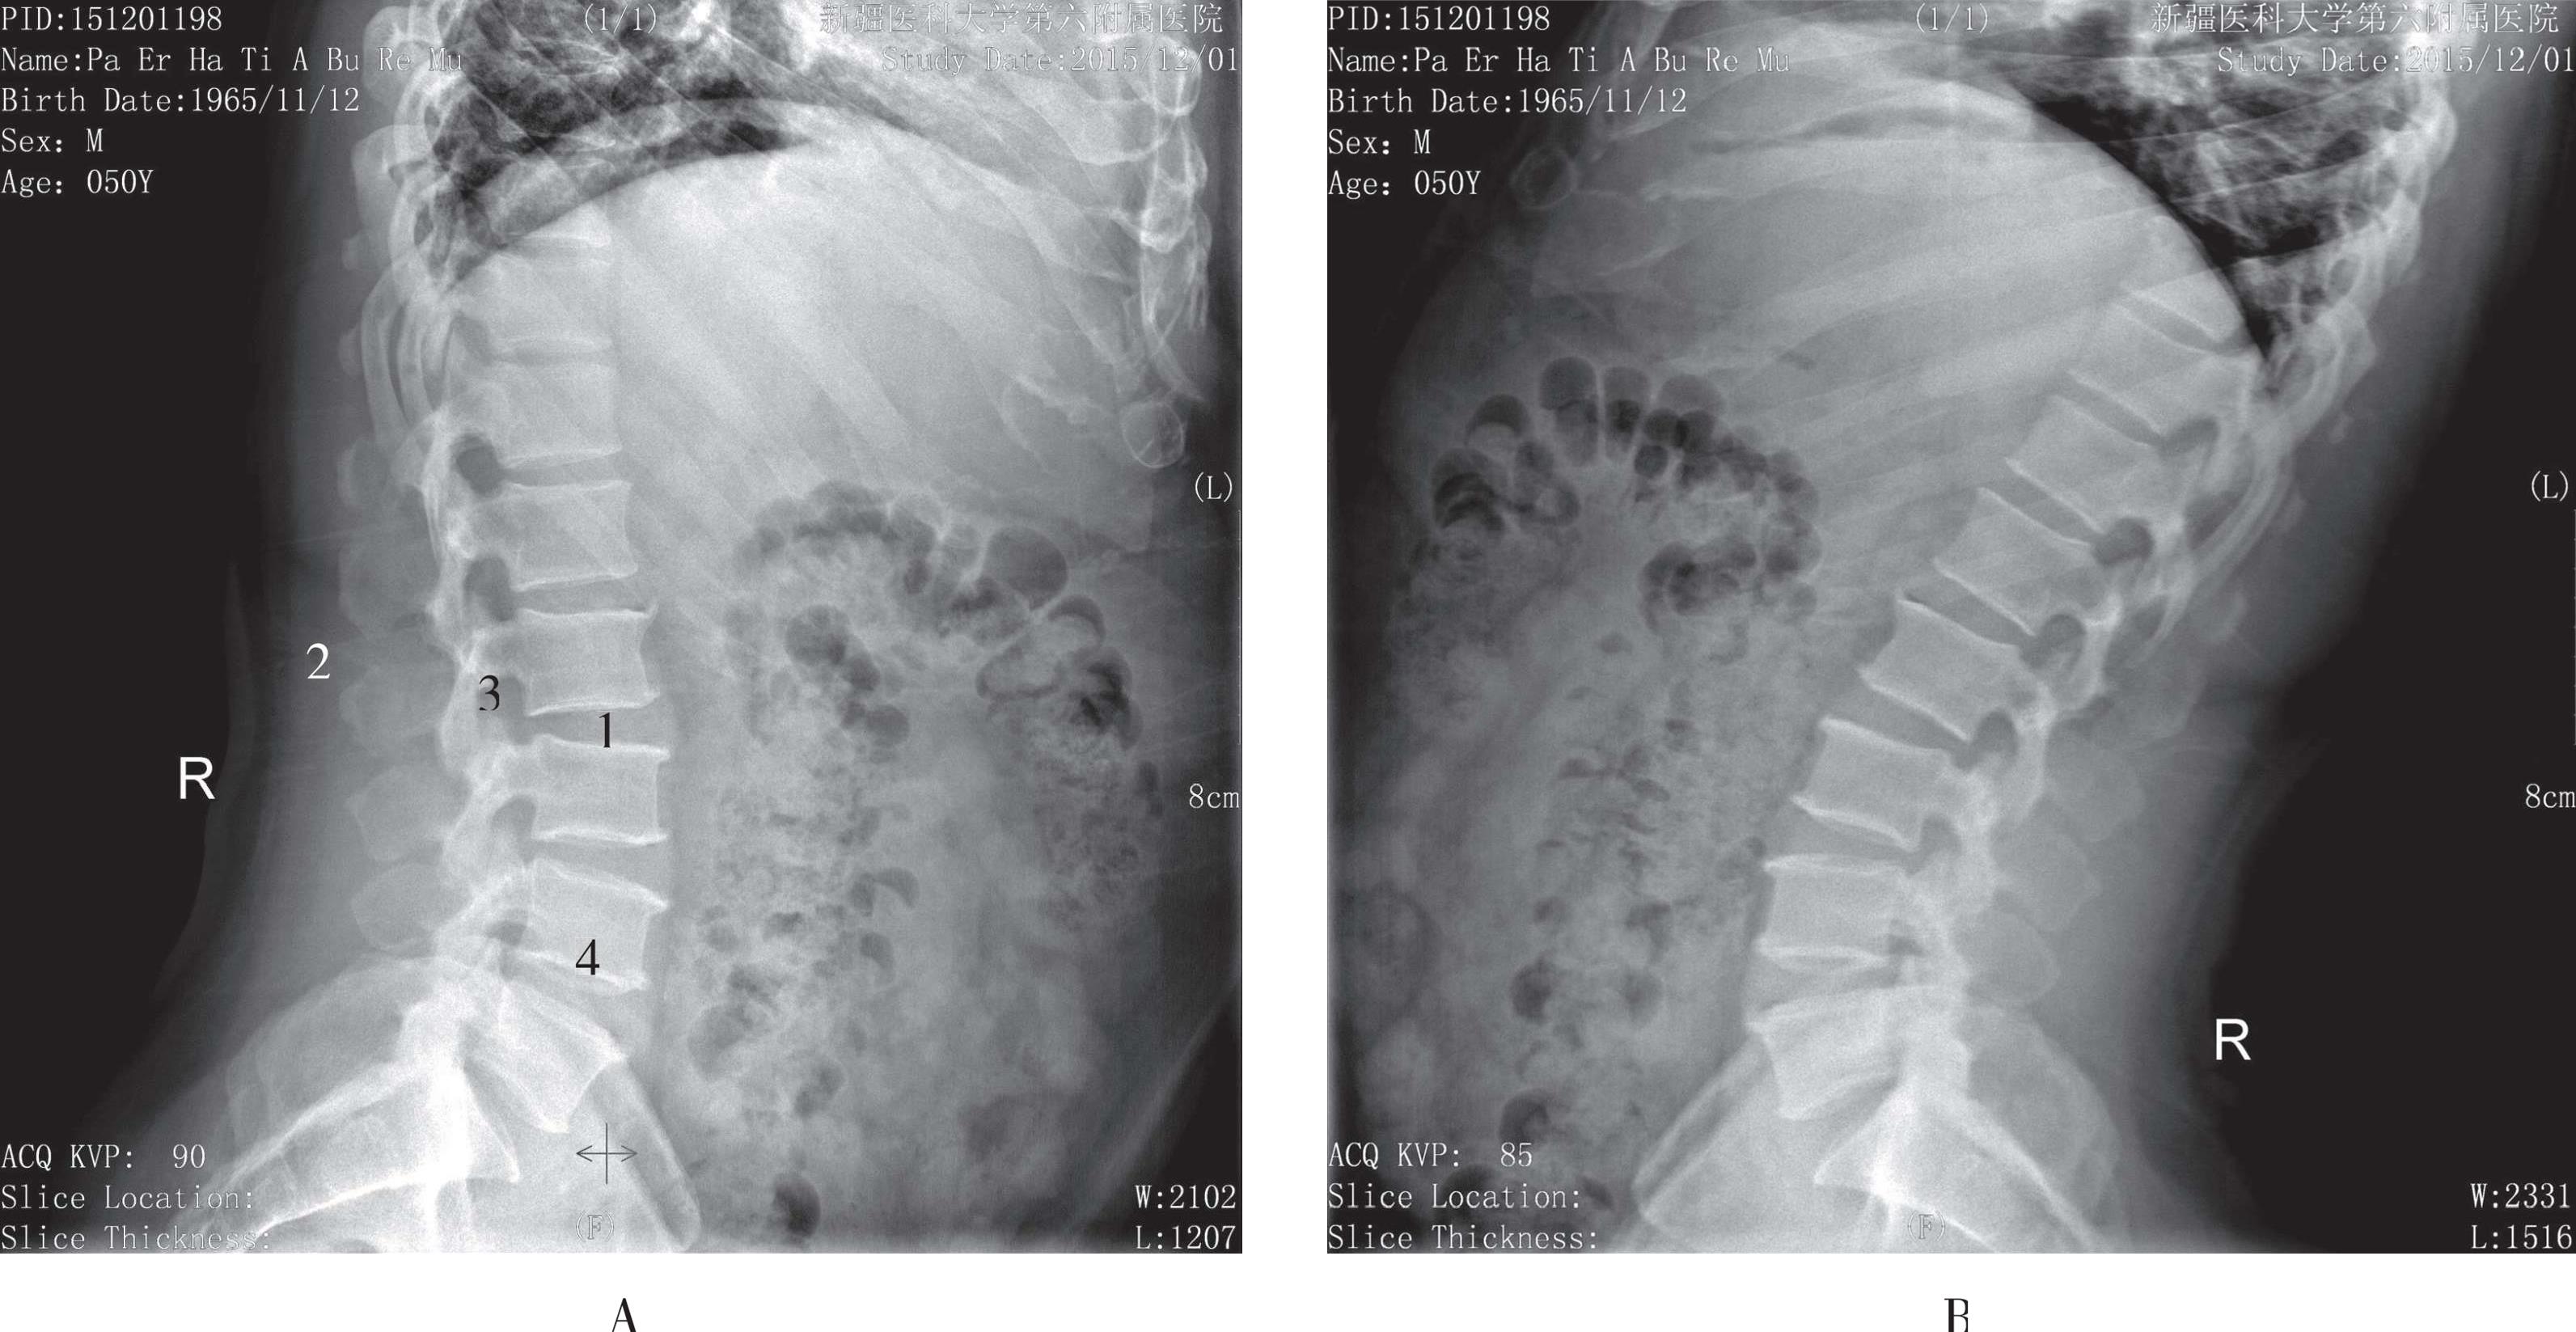

被检者立位,紧贴成像板,双手抱头,两脚稍分开站立,身体冠状面与成像板垂直,矢状面与成像板平行,身体尽量向前弯曲或向后弯曲,中心线对准腋后线L 3 垂直射入。影像显示腰椎前后缘呈光滑连续的弧线,椎弓根、椎间孔、椎间关节及棘突显示清晰,椎间隙较正位片显示清晰,骨皮质及骨小梁显示良好(图3-16)。

A. 腰椎过屈位片;B. 腰椎过伸位片。1. 椎间隙;2. 背部软组织;3. 椎弓;4. 椎体

图3-16 腰椎过伸过屈位片